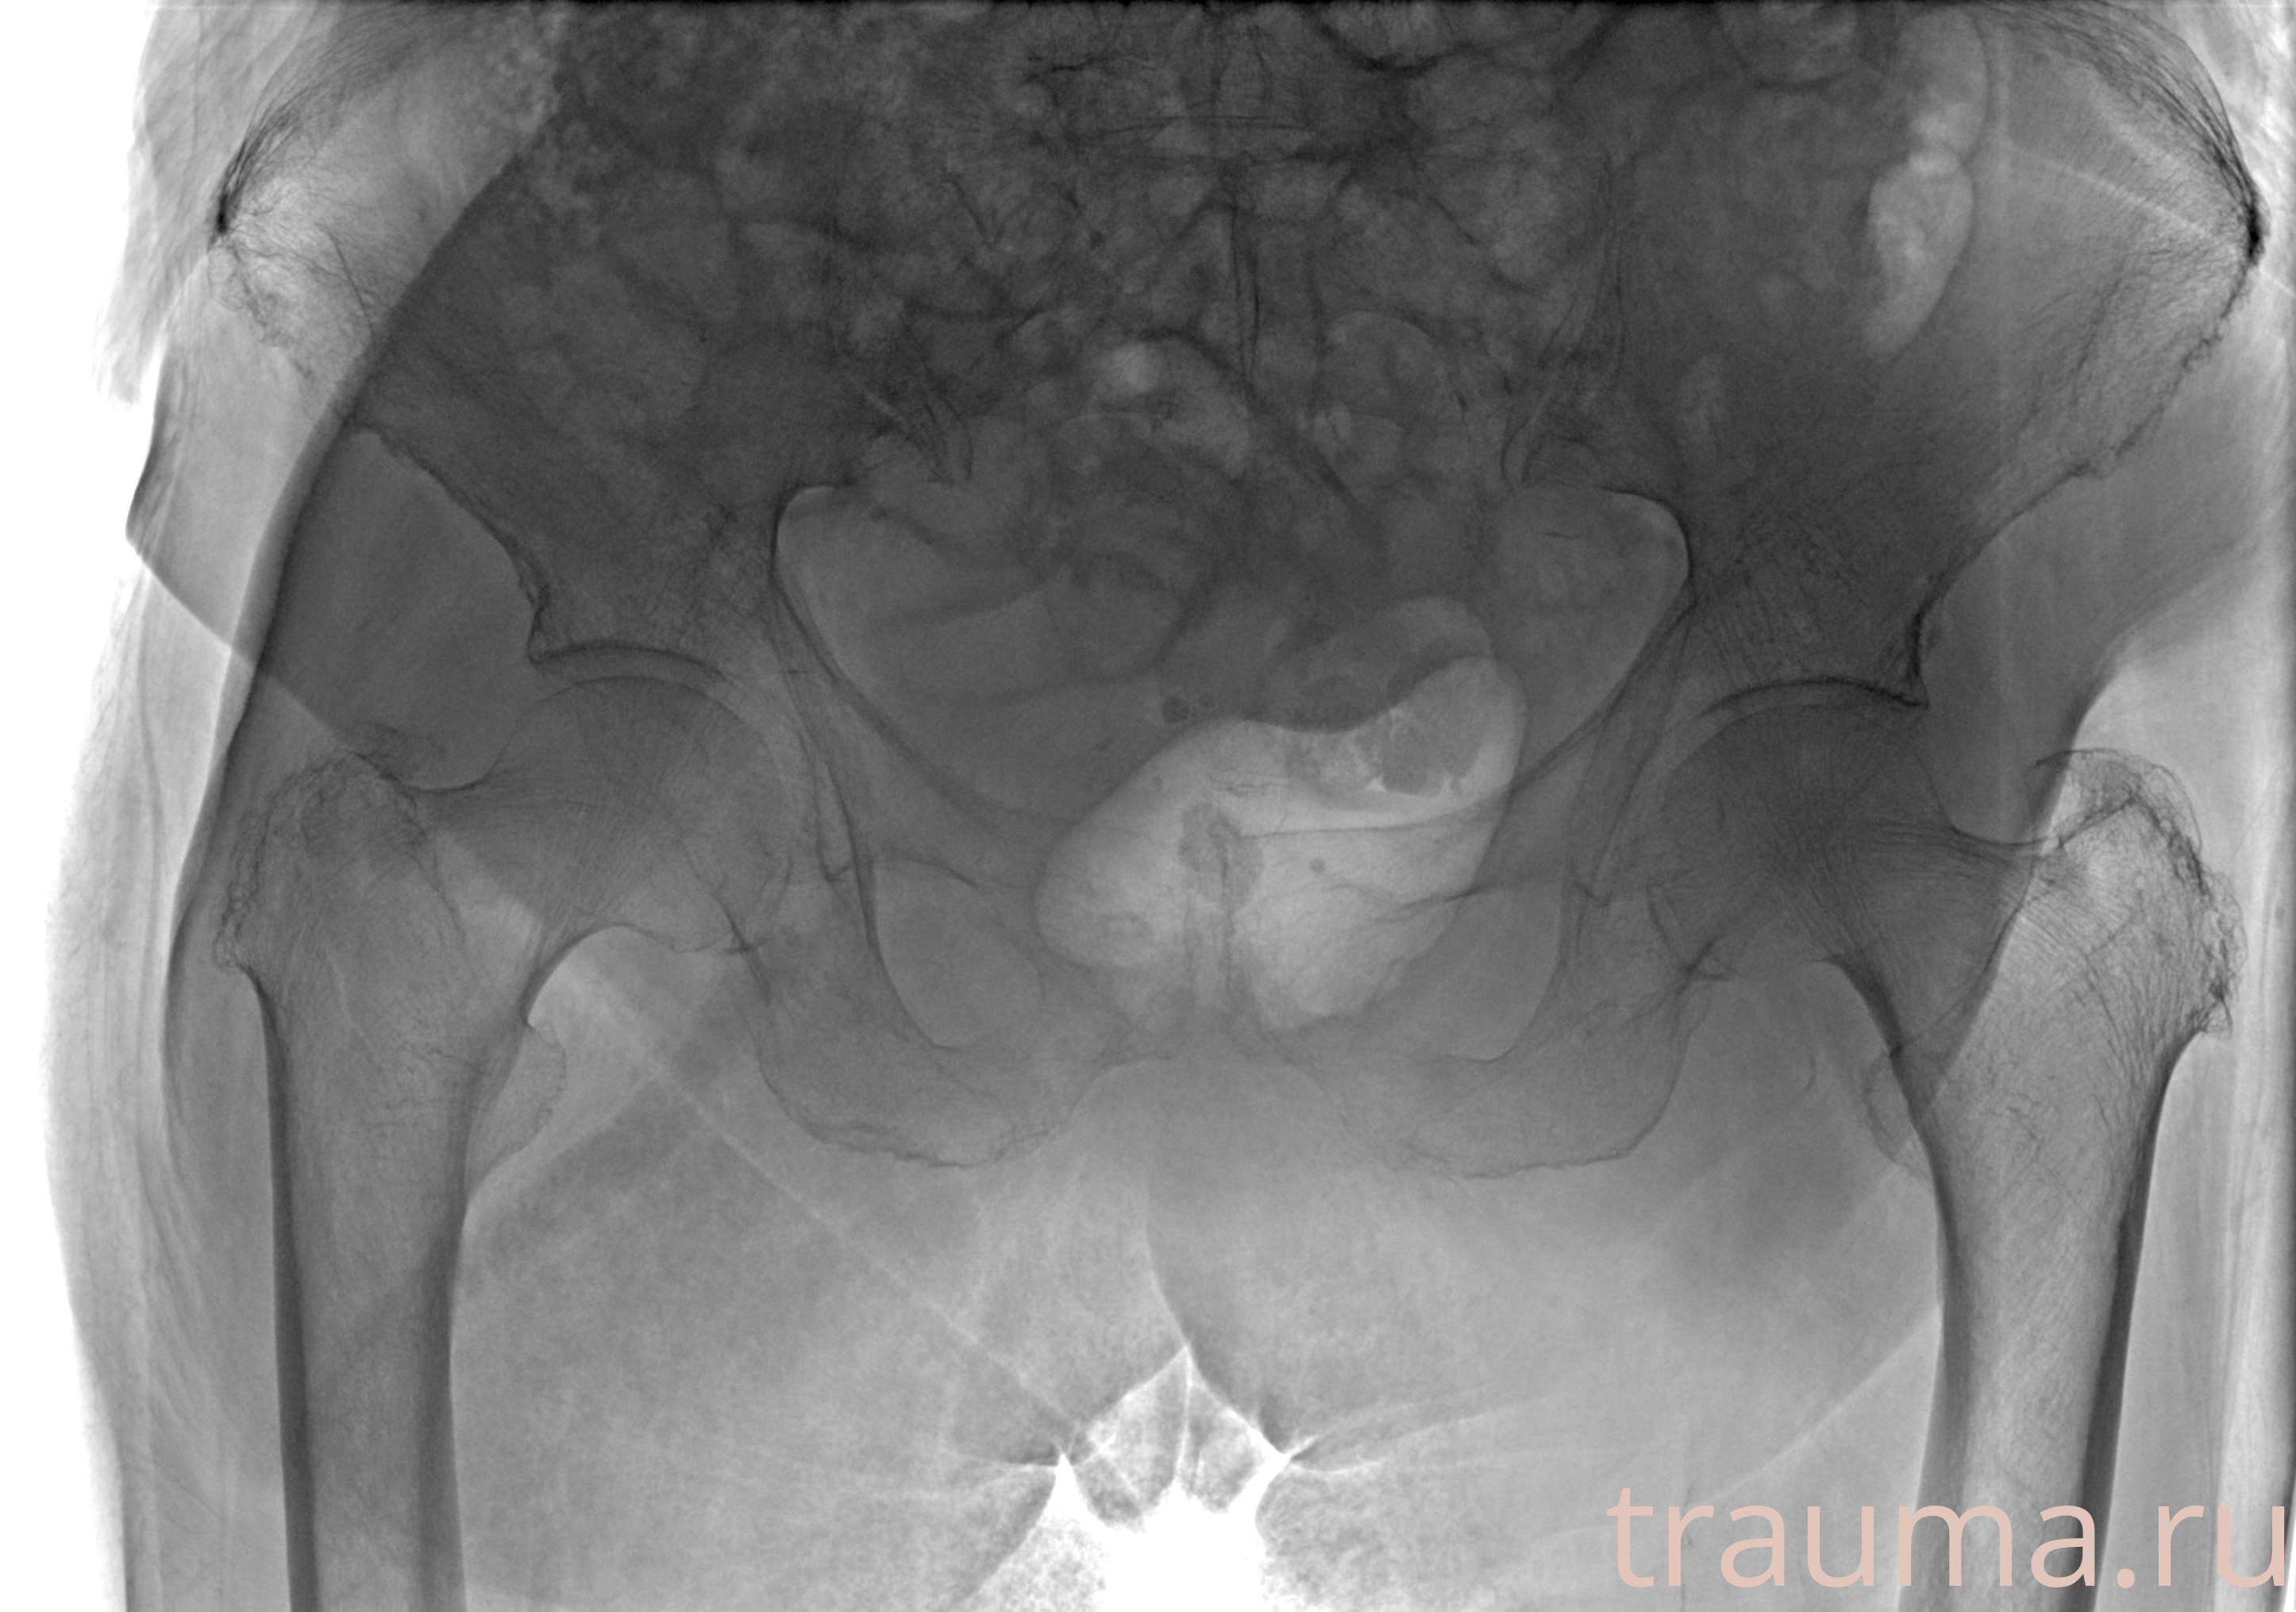

Рентгенограммы

Рентген на дому: по вашему адресу приезжает врач-рентгенолог, травматолог-ортопед с мобильным рентгеновским аппаратом, проводит диагностику травмы или заболевания, делает необходимые рентгенограммы, дает рекомендации по дальнейшему лечению. Получить качественные снимки в домашних условиях возможно благодаря уникальной методике, разработанной МосРентген Центром для института  Склифосовского